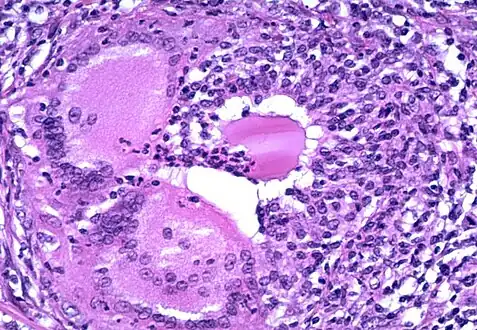

a) Grade 1 thyroiditis characterized by presence of increased number of lymphocytes b) Grade 2 thyroiditis shows the presence of Hurthle cells, epithelioid cells, giant cells, and anisonucleosis c) Grade 2 thyroiditis shows the presence of Hurthle cells with lymphocytic infiltration d) Grade 3 thyroiditis characterized by presence of florid lymphocytic infiltration -

Microscopic image showing inflammation of the thyroid tissue